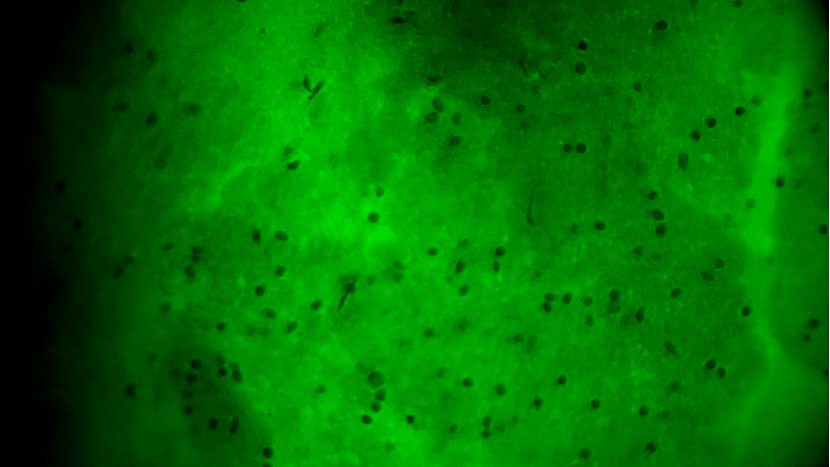

術(shù)中EndoSCell?細(xì)胞圖像如下:

腫瘤邊緣區(qū)域:個(gè)別細(xì)胞核存在異型性,密度下降,分布不規(guī)則,陽性。